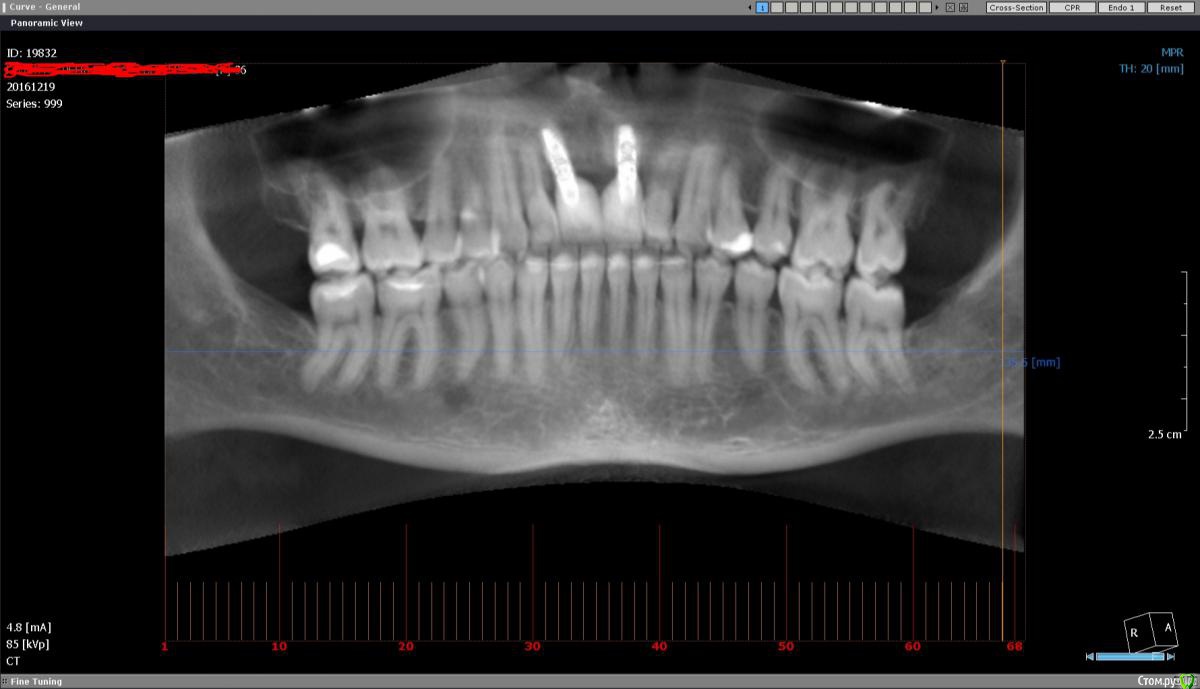

ЕленаR Опубликовано 20 ноября, 2016 Поделиться Опубликовано 20 ноября, 2016 (изменено) Добрый день уважаемые врачи. С момента своей имплантации возвращаюсь и возвращаюсь сюда. По сути: в детстве попала в аварию, две верхних единички выбила. В то время выход был только один-мост на двойки. В 32 года решила установить импланты, и вот мне уже почти 37, а я все лечусь. Врач говорил, что все будет окей, и я согласилась на имплантацию не думая, что будет все так сложно. Про мытарства во время имплантации писать не буду, они были все время. Не один из этапов имплантации не прошел без косяков. Но суть не в этом. Через 1,5 - 2 года импланты были установлены, но при этом шатались двойки! Отчего такое может быть? Сейчас они укрепились, но не так как раньше. Импланты выглядят как зубы лошади. Коронки были установлены очень высоко, терапевт этой же клиники даже как-то спросил кто так установил импланты под самый гребень. Спасает только то, что улыбка у меня закрытая, не десневая. Прошел год, десна над имплантами поднялась. На чистки езжу регулярно, врач сказал ничего страшного потом закроем. Но над одним из имплантов пошло воспаление. Пришлось срочно ехать в клинику. Врач предположил, что воспаление началось из-за того что переохладилась, и из-за того что лезу туда зубной щеткой (а как тогда чистить зубы не представляю) назначили операцию. Операцию делал другой врач, пояснил что у меня тонкий фенотип десны, и они решили нарастить мне лоскут . Лоскут нарастили. И вот прошло три месяца , имплант начал болеть. Болит как настоящий зуб. Пропила антибиотки болеть перестал. В клинику где мне устанавливали импланты я больше ни ногой. Могут ли мне удалить импланты в другой клинике или надо обращаться где ставили? Очень ли это болезненная и травмирующая процедура? Записалась по интернету в две клинике на прием. Ответ пришел, что у меня сложная ситуация будут смотреть. Все это время думала, что это у доктора не хватило опыта мне сделать имплантацию во фронте как положено. Сейчас начинаю сомневаться, что если все так сложно, не возникнет ли повторение ситуации? Может тот доктор сделал все что было в силах в моей ситуации. Задумываюсь о другом виде протезирования. Но двойки у меня стали очень слабые. Если ставить мост и захватить клыки, будет ли такая конструкция устойчива? смогу ли я такими зубами кусать без проблем? Или может быть сделать какой-нибудь протез на замках? Боюсь сделать не правильный шаг и навредить себе еще больше. Проблема не только в эстетике, но еще и в способности откусывать пищу. Когда стоял мост на двойках это было проблемой. Посоветуйте пожалуйста как лучше поступить. Мост с захватом клыков, протез на замках или попытка новой имплантации? Снимок сделан три месяца назад до операции. Изменено 20 ноября, 2016 пользователем ЕленаR Ссылка на комментарий

ЕленаR Опубликовано 21 декабря, 2016 Автор Поделиться Опубликовано 21 декабря, 2016 Добрый день. Уже все сделано и нет пути назад. Но хочется услышать ваше мнение и поделиться продолжением своей эпопеи. На приеме врач сразу отправил на КТ.глядя снимки, предположил, что один имплант не стабилен.Поэтому предыдущие врачи сделали сдвоенную коронку. Также сказал, что противник чтобы подсаживали свой костный блок во фронт. Сколько здесь писала про это, никого не удивляло, что мне блок во фронт подсадили. Вообщем вчера мне удалили два импланта, вытаскивали, как мне показалось с трудом. Врач сказал, что импланты стояли в кости на 2/3 и обросли фиброзной тканью. Мне сразу установили два импланта суперлайн и поставили формирователи. Через два дня будут ставить временные коронки, через 3 месяца постоянные. КТ пока выложить не могу, в наличии только тел. Уважаемые специалисты, как вы думаете такой план лечения имеет место быть? И импланты суперлайн хорошо система, это не миниимпланты? До этого стояли xive. Удивило то, что если имплант был меньше чем на половину в кости, почему его так выбивали.Это нормально? Извините за сумбур. Доктор вроде адекватный, но так страшно попасть не в те руки опять. Ссылка на комментарий